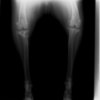

アメリカンコッカースパニエル 5歳

半年にわたる左後肢の跛行が認められるとのことで来院されました。触診にて左膝関節の疼痛、内側部の腫脹、膝蓋骨の内方脱臼を認めました。レントゲン検査にてfat pad signを伴う関節炎が認められたことから、前十字靭帯断裂と膝蓋骨内方脱臼( GradeⅢ)の併発と診断し、手術を行いました。術中の関節鏡検査にて前十字靭帯の完全断裂を確認、関節液検査にて感染を除外した後、TPLOと、滑車溝形成を始めとした膝蓋骨脱臼整復術を実施いたしました。

術前側面像

術前正面像

術後側面像

術後正面像

術前に25°であったTPAは、TPLO実施により7°に矯正されました。症例の歩行状態は良好です。